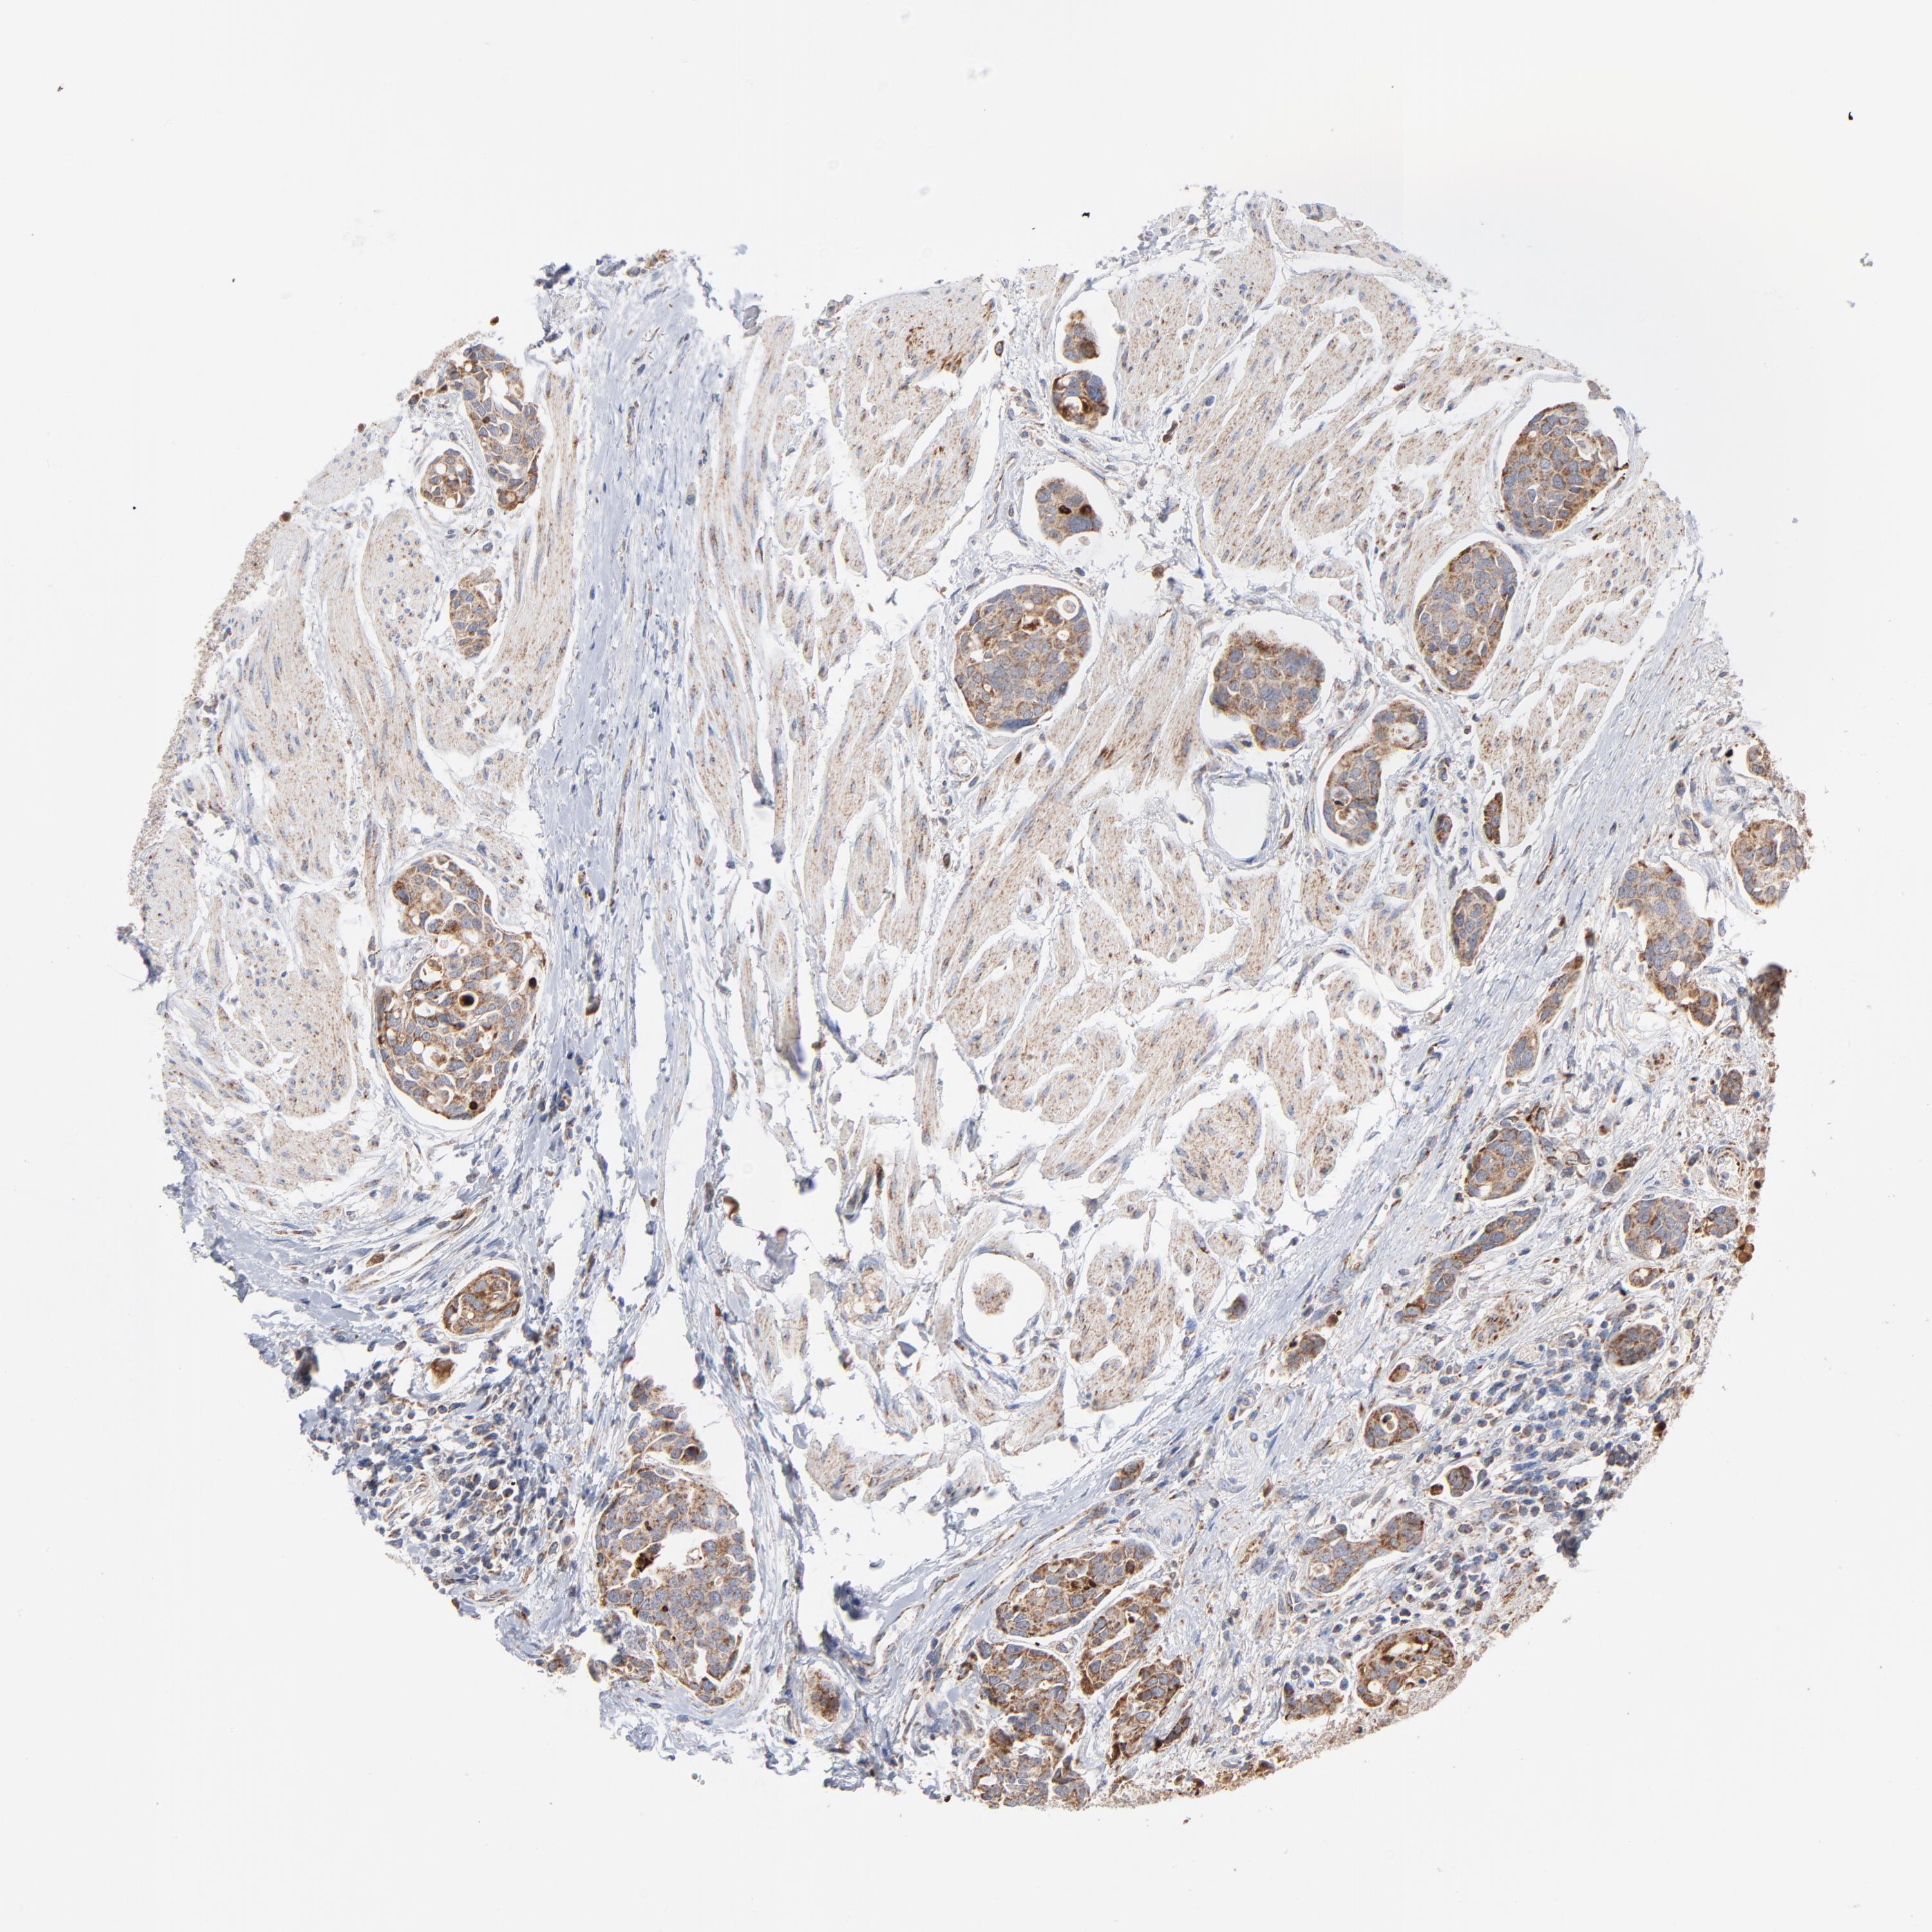

UROTHELIAL CANCER - Protein expressioni

A mouse-over function shows sample information and annotation data. Click on an image to view it in a full screen mode. Samples can be filtered based on level of antibody staining by selecting one or several of the following categories: high, medium, low and not detected. The assay and annotation is described here.

Antibody stainingi

Antibody staining in the annotated cell types in the current human tissue is reported as not detected, low, medium, or high, based on conventional immunohistochemistry profiling in selected tissues. This score is based on the combination of the staining intensity and fraction of stained cells.

Each image is clickable and will lead to virtual microscopy that enables deeper exploration of all samples and also displays staining intensity scores, fraction scores and subcellular localization as well as patient and tissue information for each sample.

Antibody HPA001825

Antibody CAB003857

Urothelial carcinoma, High grade